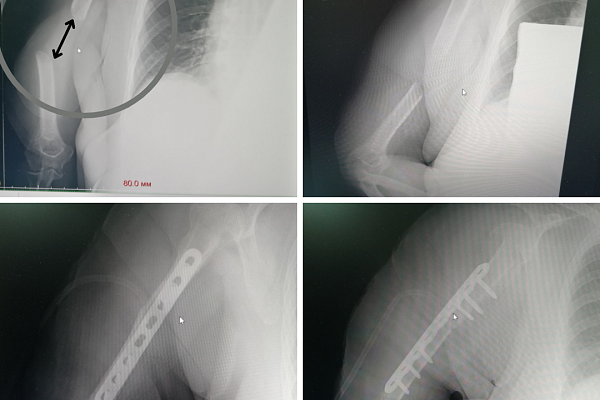

В Сургутской травмбольнице широко применяется и другой вид остеосинтеза – накостный, когда отломки собираются пластинами. В данном случае специалисты посчитали его слишком травматичным методом лечения. Зато другой пациентке он подошёл идеально. Тоже не являясь югорчанкой, пожилая женщина доверилась именно нашим врачам. Перелом плечевой кости – самый обычный. Вот только условия для его сращения своевременно обеспечены не были. В итоге под силой тяжести костные отломки разошлись на большое расстояние друг от друга, и лишившаяся опоры рука повисла на мягких тканях, как плеть.

– При свежем переломе операция заняла бы минут сорок. Но нам достался уже запущенный случай с большим диастазом. Доступ затруднял сосудисто-нервный пучок и сформировавшиеся рубцы, которые необходимо было зачищать. Тем не менее, до перелома добрались, с помощью пластин восстановили кость и её ось. Несмотря на упущенное время и возраст пациентки, вероятность сращения велика, – отмечает Евгений Бойко.